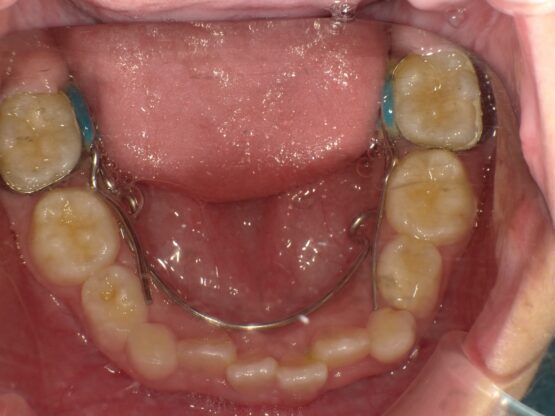

急速拡大装置で上顎の拡大が進むと、下顎の骨も調整する必要が出てきます。その際に使う装置がリンガルアーチです。下顎の骨は上顎の骨と作りが違います。下顎はひとつの骨で構成されているので、上顎と同じように拡大させることができません。内側に傾いている歯を起こすようにして歯列部分だけを拡げていきます。この装置も固定式の装置となっており、歯の裏側に装着しますので目立たない見た目となっています。